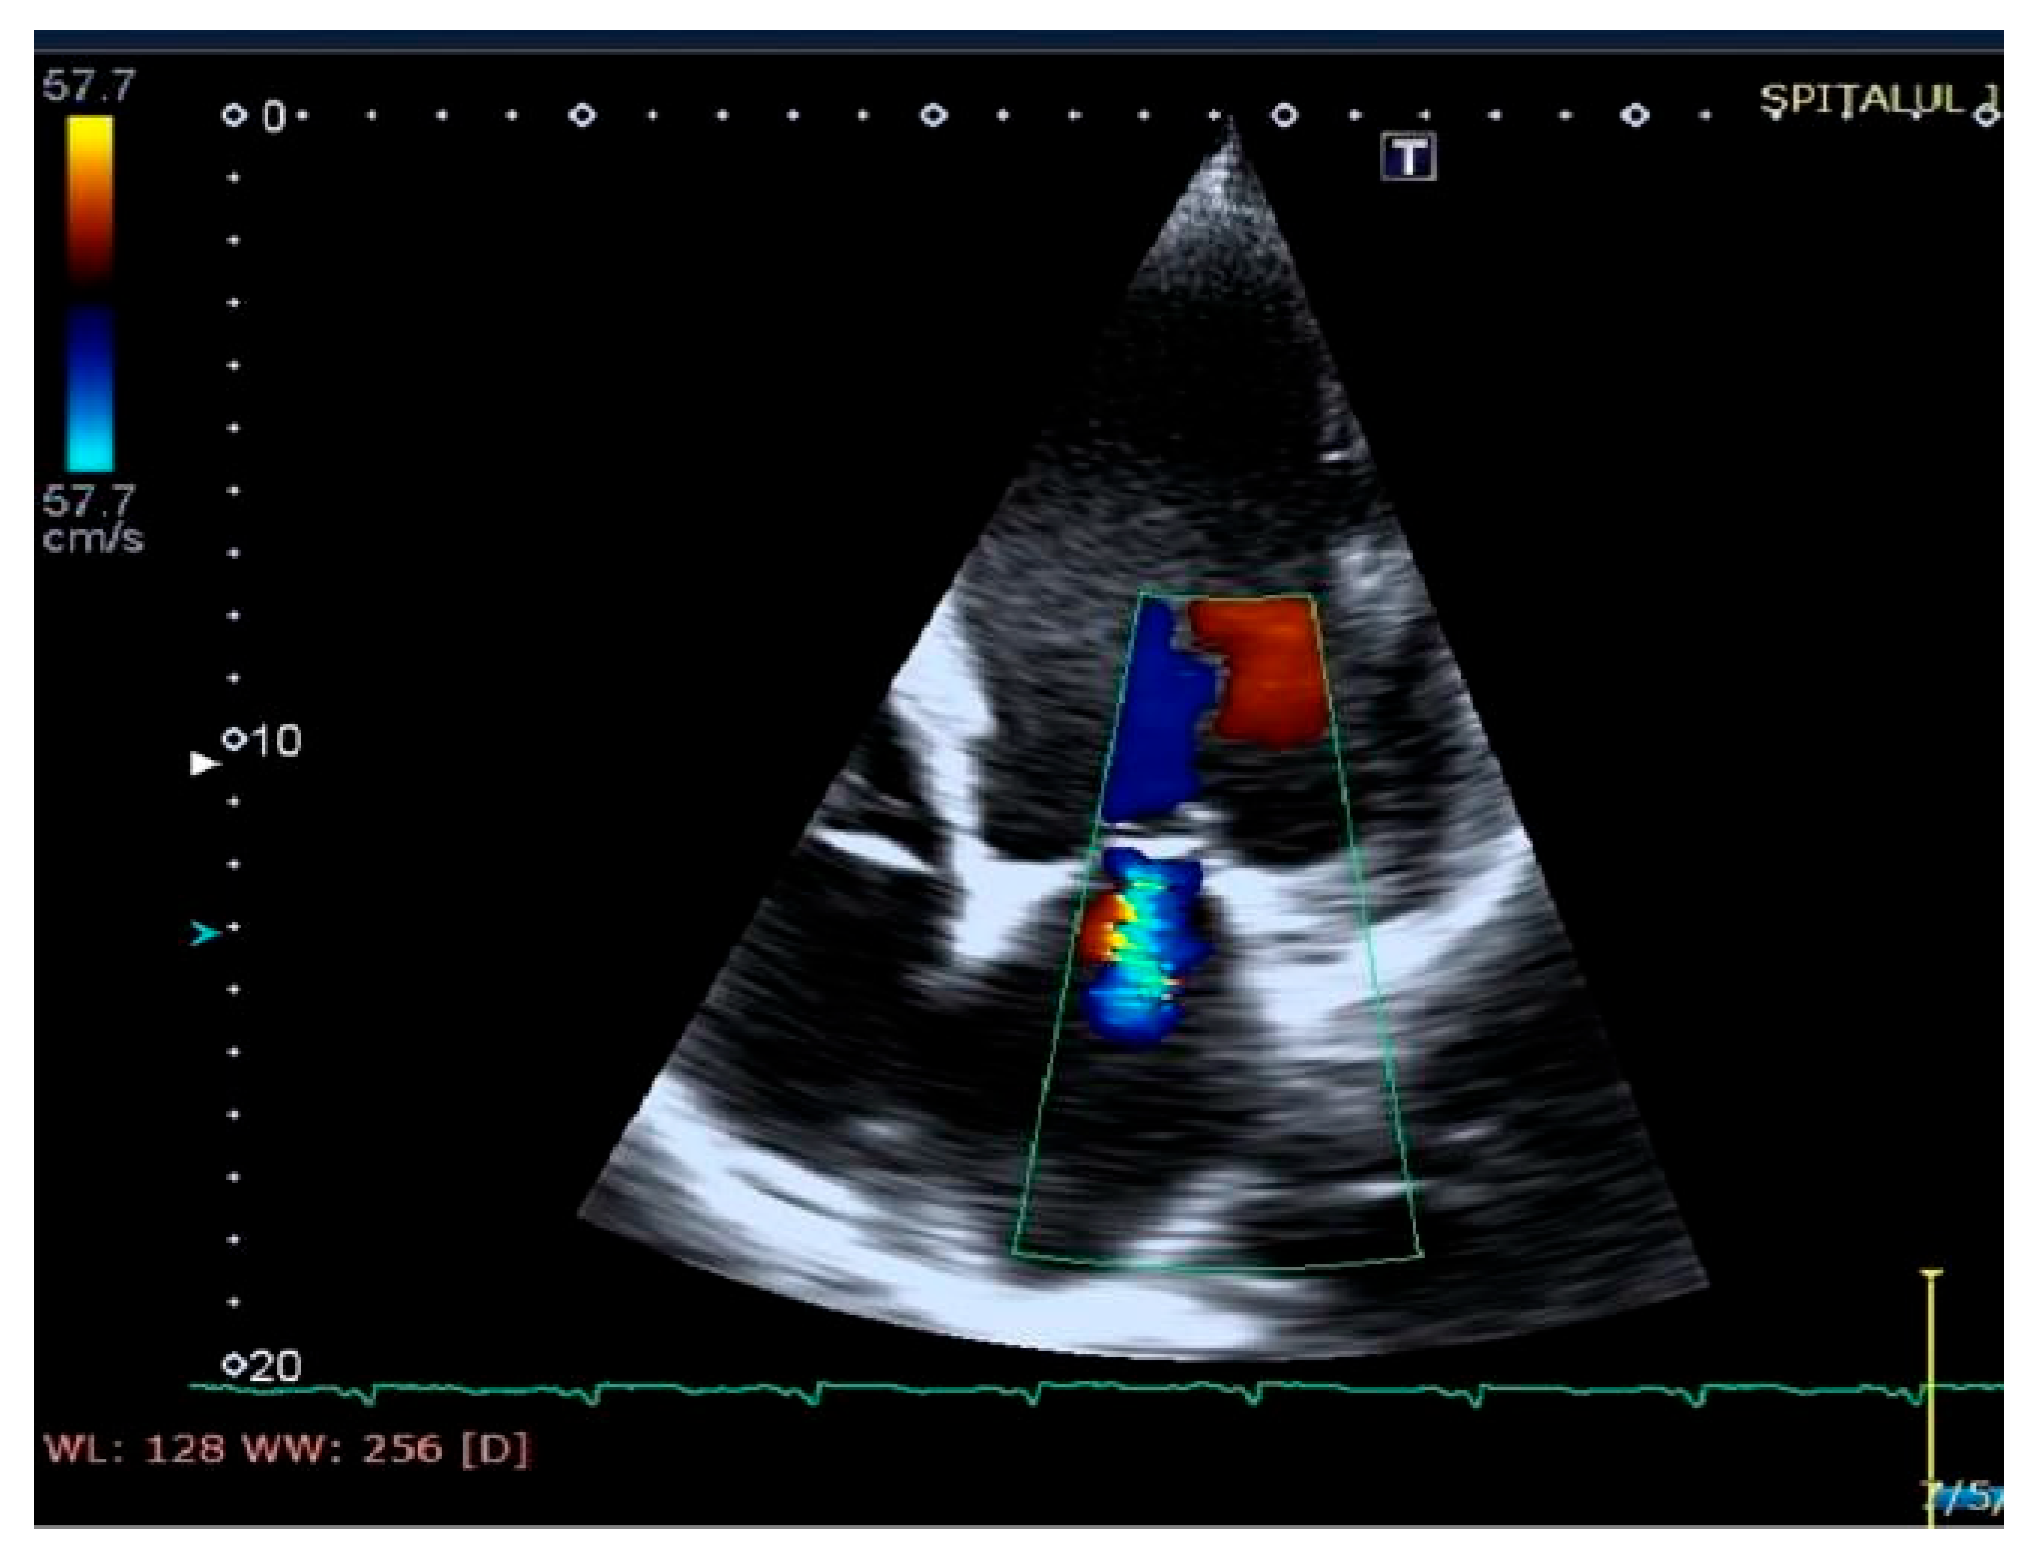

Mitral regurgitation (highlighted as multicolored mosaic pattern, green and yellow), after therapy with a cardiac resynchronization device.

Figure 8.